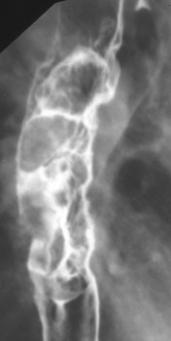

Stade avance un

cancer de oesophage de forme infiltrant . La longeur

de la tumeur depasse 5mm |